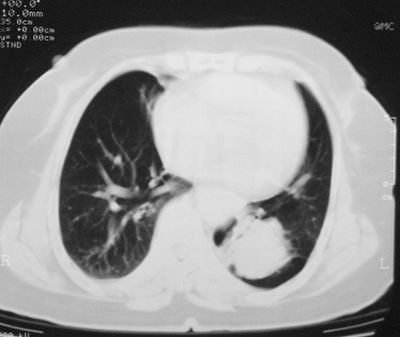

本次复查胸部ct

左下肺软组织块影,有分叶、毛刺、空泡及胸膜牵拉征,左下肺周围性肺癌。

左肺下叶周围型肺癌,支持!(软组织肿块+分叶+毛刺+空泡+胸膜凹陷征)

左下肺软组织密度影,可见分叶,边缘可见毛刺征,胸膜增厚,强烈要求左下肺周围型肺癌

左下肺后基底段实性肿块,周围有毛刺,病变周围有肺气肿,与降主动脉间有条带状影相连,病灶4年前查体发现,纵隔内未见肿大淋巴结。考虑.肺隔离症,建议增强扫描与周围型肺癌鉴别。